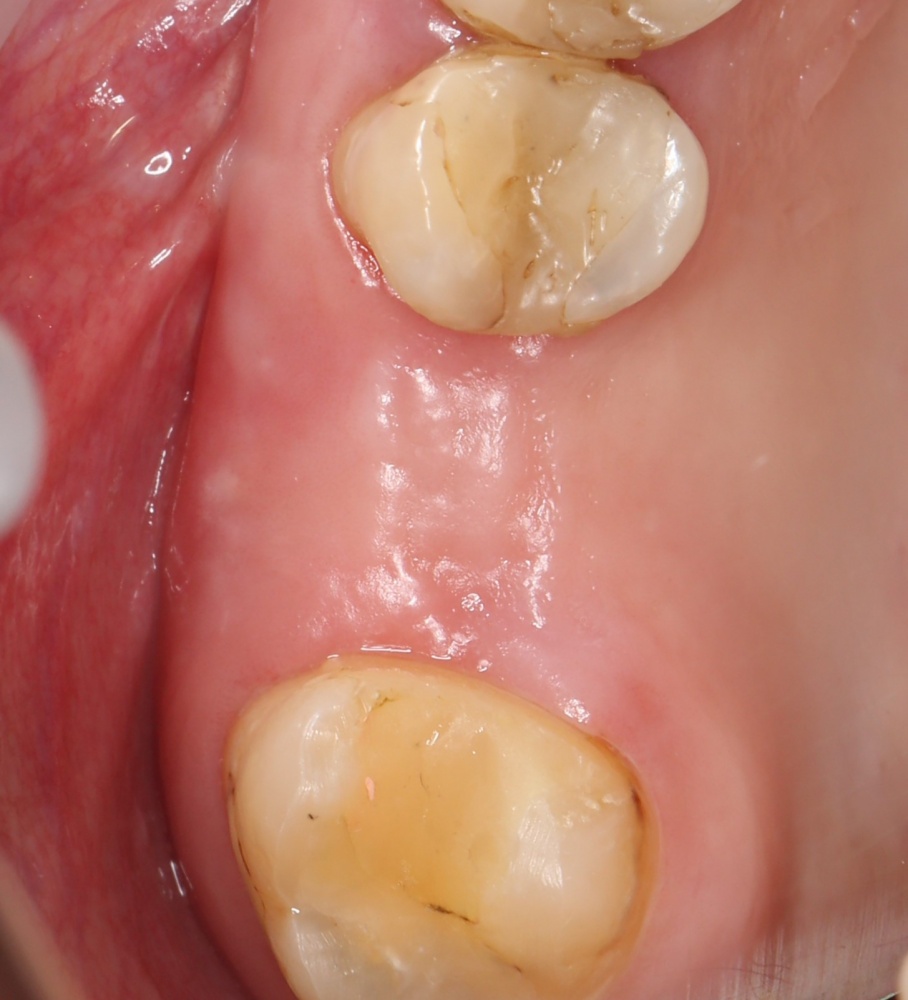

Рекомендации по установке имплантов. Для всех. Часть V.